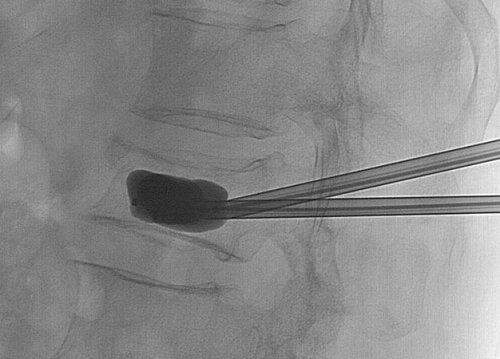

- Xác định đốt sống thương tổn dưới C-Arm. Đưa kim chuyên dụng đi vào chân cung ở vùng ¼ trên – ngoài trên bình diện thẳng. Kiểm tra vị trí kim trên 2 bình diện: thẳng và nghiêng, đảm bảo hoàn toàn kim sẽ nằm trong chân cung và thân sống. Đưa kim vào thân sống đến vị trí 1/3 trước thân đốt sống với loại không bóng.

- Cement (PolyMethylMethAcrylate-PMMA) bơm vào thân sống khoảng 4 – 8 ml, quá trình này được kiểm soát liên tục dưới C-Arm để tránh cement dò ra xung quanh.